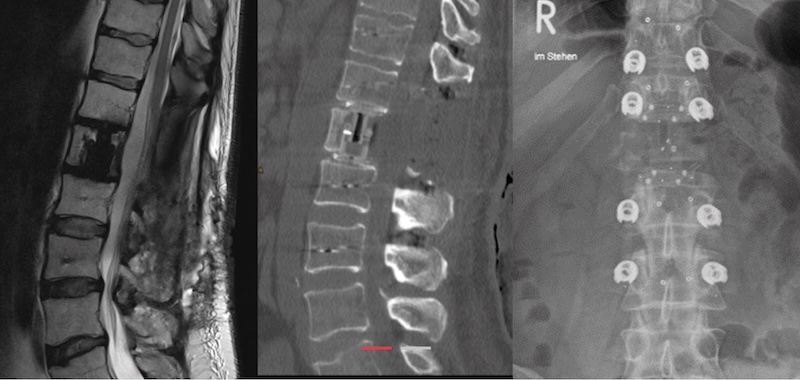

By Procedure Type: Thoraco-lumbar Corpectomy

By System Type: Deformity , Oncology

The KONG -TL VBR System by icotec Medical is an expandable corpectomy spacer composed of radiolucent carbon fiber and PEEK materail that features titanium coated endplates for increased bony integration. The KONG -TL is intended for use in the thoracolumbar spine and features modular endplates of various sizes, shapes and lordosis options. Endplates are secured via a carbon-fiber/PEEK screw